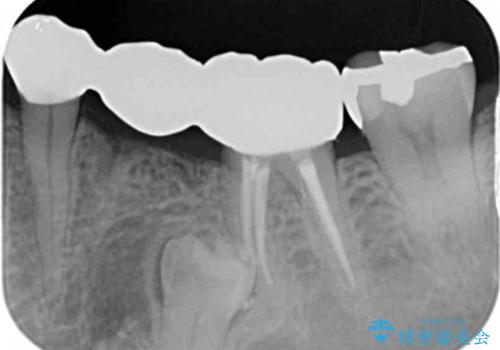

- 大人になってからも残っていた乳歯が揺れ始め、抜歯を覚悟しインプラント治療を希望して来院されました。

X線写真より、乳歯は抜歯が必要な状態でインプラントは小臼歯の埋伏により難しい状況であったのでブリッジによる補綴を選択しました。

ブリッジ治療の予知性を高めるために、虫歯の徹底的な除去に加え縁上歯質を確保するための歯周外科手術、マイクロスコープを用いた精密根管治療を行う治療計画としました。

- 26万円(仮歯・ファイバーコア・フルジルコニアクラウン×3) 費用は治療当時の料金となります